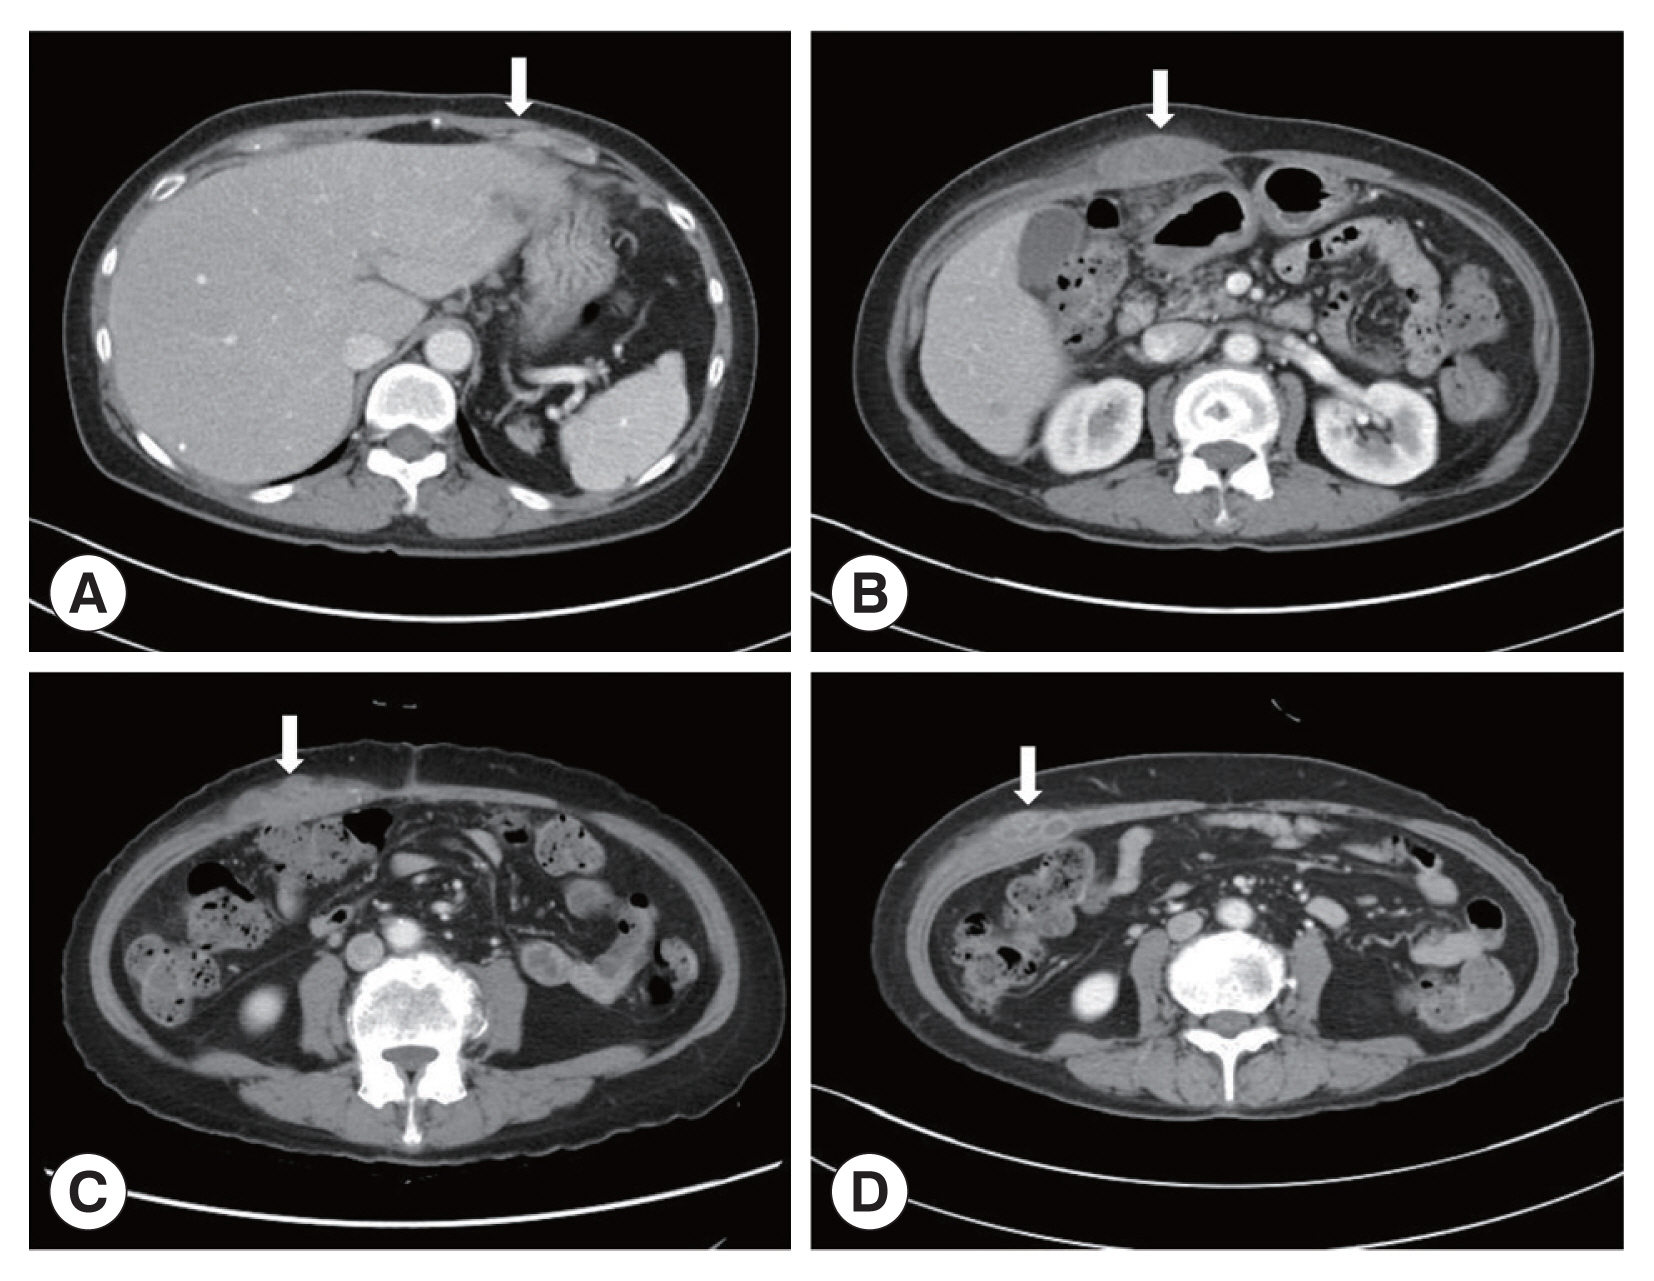

A 66-year-old Korean woman living in Pusan visited the Pusan National University Hospital on July 11, 2021, with an abdominal mass. She had been suffered from hypothyroidism. In June 2021, she was diagnosed with a hepatic abscess by computed tomography (CT) performed during an evaluation of RUQ pain at another hospital. The symptoms improved by symptomatic treatment and she was discharged after administration of antibiotics (ceftriaxone and metronidazole) (

Fig. 1A). She visited again our hospital due to recurrence of the RUQ pain. The mass was palpable in the abdominal cavity, we checked the mas with CT. Some swelling and cell infiltration was confirmed, and parasitic infection was suspected (

Fig. 1B). She received praziquantel (25 mg/kg 3 days). Most fascioliasis patients showed eosinophilia and abdominal distension [

11]. Abdominal distension along with eosinophilia was also confirmed in this patient. In August 2021, liver abscess was percutaneously drained, after which she was discharged. However, she complained of new pain in the subcostal region (

Fig. 1C). Praziquantel treatment were maintained, but her symptoms did not improve. New multiple abscesses were found below the previous lesion on abdominal CT. Compared to the previous CT, a lateral movement of the abscess was observed with maximum size of 3.4 cm (

Fig. 1D). The CT showed abdominal distension. The laboratory test showed eosinophilia (7.3%, normal range 0–6.9%) with low number of segmented neutrophil (38.8%, normal range 40.0–70.4%). The mean corpuscular hemoglobin concentration, eosinophil count, and erythrocyte sedimentation rate increased, and the levels of seg neutrophils decreased. A biopsy revealed a leave-like parasite. The length was approximately 1.7–1.8-long, and the width was 0.5–0.8-long. The morphology of the posterior testis of the

Fig. 1Abdominal computerized tomography (CT). (A) CT performed at the time of admission for evaluation of pain in the right upper quadrant (RUQ). (B) RUQ pain recurred after treatment of liver abscess. CT was taken to evaluate the abdominal wall mass. (C) Abdominal CT performed with new pain in the subcostal area. (D) There was no improvement after maintenance treatment with praziquantel. CT was taken again at Pusan National University Hospital. The arrows indicated a mass lesion.